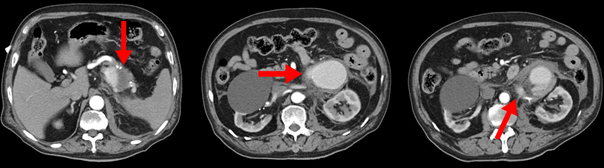

病例资料(男性,85岁)

主诉:左腰部疼痛15小时余

既往史:高血压病史,急诊血压100/60 mmHg、心率120次/分

实验室检查:血常规:Hb 75 g/L,Hct 25%,RBC 2.5×109/L;血凝正常

超声:脾动脉瘤可能

CTA:脾动脉瘤,约8×5×7 cm,破裂可能

图片